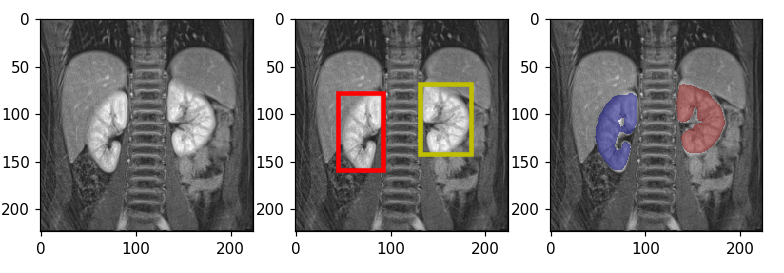

To optimize the parameters of the proposed framework for automated segmentation of normal and abnormal kidneys, we performed cross validation experiments on 24 subjects (10 with normal and 14 with abnormal kidneys). We used precision, recall, dice coefficient (DSC) or F1-score and volumetric estimation error (VEE) for evaluating the algorithm segmentation performance. F1-score, which is the harmonic average of precision and recall, reports the accuracy of the overlap between the predicted and true manual segmentation. We also report the performance of the model, trained using 24 subjects, and tested on 12 kidneys from 6 previously unseen subjects (3 patients with normal and 3 patients with pathological kidneys) that were not included in the training process. As explained in section 3, we train each of the localization and the segmentation networks independently using the training data and the manual segmentation masks. Segmentation results are shown in Figure 2 for one normal and one abnormal kidney example from the test set. Middle figure in each row is showing the result of bounding box detection. Predicted output consisted of three classes; right kidney, left kidney and background. After extracting three classes from initial segmentation masks and forming the bounding boxes, each class was scaled to volumes and the original time dimension was resampled, interpolated and added to the data as the channel information. Finally, the segmentation classifies each voxel in the high resolution image into kidney or non-kidney class. Third figure in each row is showing the result of segmentation and re-positioning each kidney back into the detected bounding box. The resulted average performance measures for final unseen test cases are reported in Table. 1. Mean F1-scores for three patients with normal and three with abnormal kidneys were and respectively.

(a) Normal Kidney (F1-score: 94.63 )